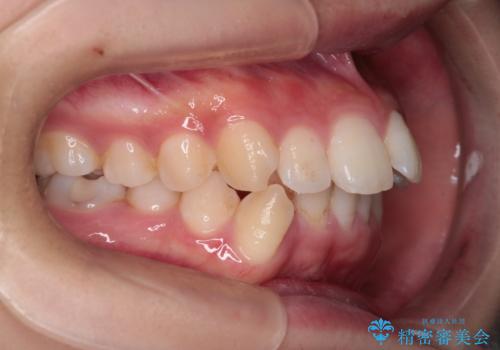

重度の歯のがたつきを、目立たない矯正と抜歯で根本改善

- 前歯から奥歯にかけて歯の重なりが激しい歯のがたつき(重度叢生)を主訴にご来院されました。精密検査の結果、歯が並ぶスペースが大幅に不足しており、歯並びを整え、口元を美しく引っ込めるためには、スペースの確保が必要と診断しました。そこで、上下左右の第一小臼歯(4番目の歯)を計4本抜歯し、そのスペースを利用して歯並び全体を整える抜歯矯正の治療計画を立案。装置には、透明で目立たないインビザラインを採用し、審美性と治療効果の両立を目指しました。

今回の治療では、重度の叢生を改善するため、まず計画通り上下左右4本の小臼歯を抜歯し、歯を並べるための十分なスペースを確保しました。装置には透明で取り外し可能なインビザラインを使用。抜歯によってできたスペースを最大限に活用し、マウスピースを定期的に交換しながら、デコボコを解消しつつ、前歯を効果的に後退させました。

治療の結果、長年の悩みであった重度の歯のがたつきが解消され、口元の突出感も改善。機能的にも安定し、審美的にも美しい、理想的な歯並びを獲得していただけました。